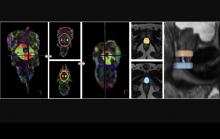

Diffusion tensor-based fiber tracking of the male urethral sphincter complex in patients undergoing radical prostatectomy

Tratografia do complexo uretral em pacientes submetidos a prostatectomia radical

No tratamento de cancro da próstata localizado, as técnicas robóticas atuais de prostatectomia radical têm vindo a demonstrar elevada precisão na remoção do tumor, bem como na preservação das estruturas em redor da próstata. Apesar destes avanços proporcionarem uma redução dos efeitos colaterais, a incontinência urinária pós-cirúrgica continua a afetar a qualidade de vida de uma percentagem significativa de pacientes com cancro da próstata.